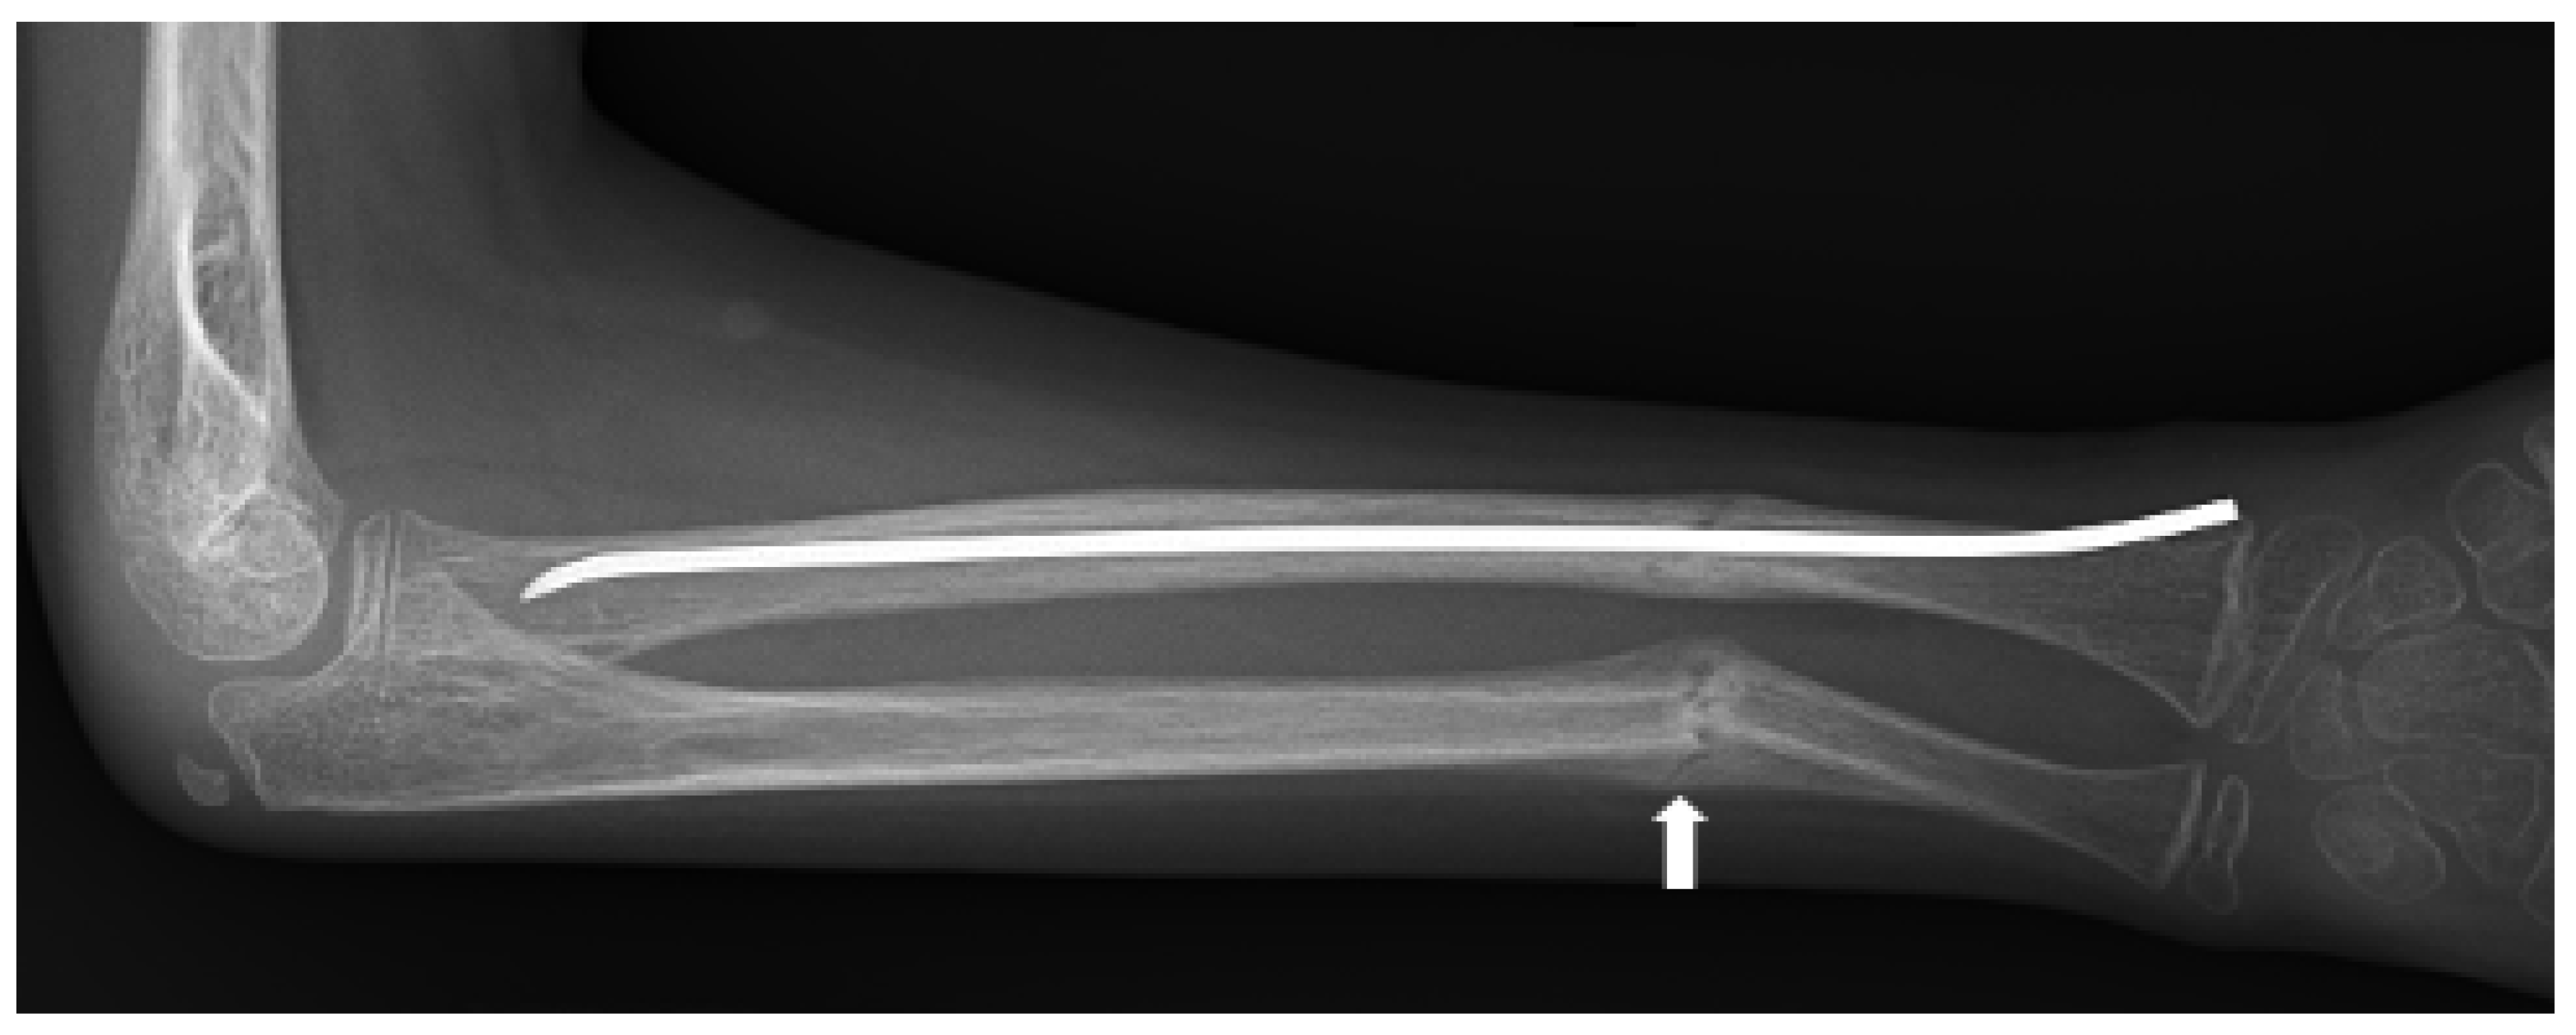

- Zhao, D.; Sun, L.; Zheng, W.; Hu, J.; Zhou, B.; Wang, O.; Jiang, Y.; Xia, W.; Xing, X.; Li, M. Novel mutation in LRP5 gene cause rare osteosclerosis: Cases studies and literature review. Mol. Genet. Genomics. 2023, 298, 683–692. [Google Scholar] [CrossRef]

- Van Wesenbeeck, L.; Cleiren, E.; Gram, J.; Beals, R.K.; Bénichou, O.; Scopelliti, D.; Key, L.; Renton, T.; Bartels, C.; Gong, Y.; et al. Six novel missense mutations in the LDL receptor-related protein 5 (LRP5) gene in different conditions with an increased bone density. Am. J. Hum. Genet. 2003, 72, 763–771. [Google Scholar] [CrossRef]